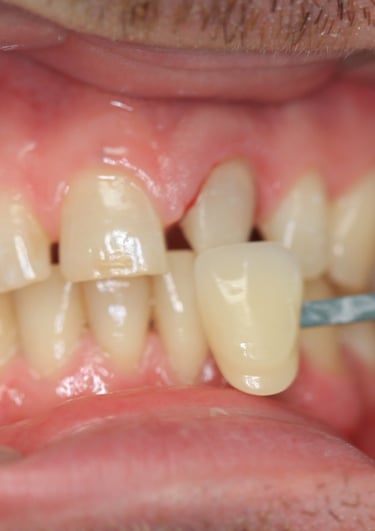

4. Prova estetica e inserimento della corona definitiva:

La nuova corona è stata prima provata per valutarne il colore, la forma e la precisione. Dopo aver ottenuto l'approvazione estetica, la corona è stata cementata utilizzando un cemento adesivo di ultima generazione, garantendo stabilità e una perfetta integrazione con i tessuti.